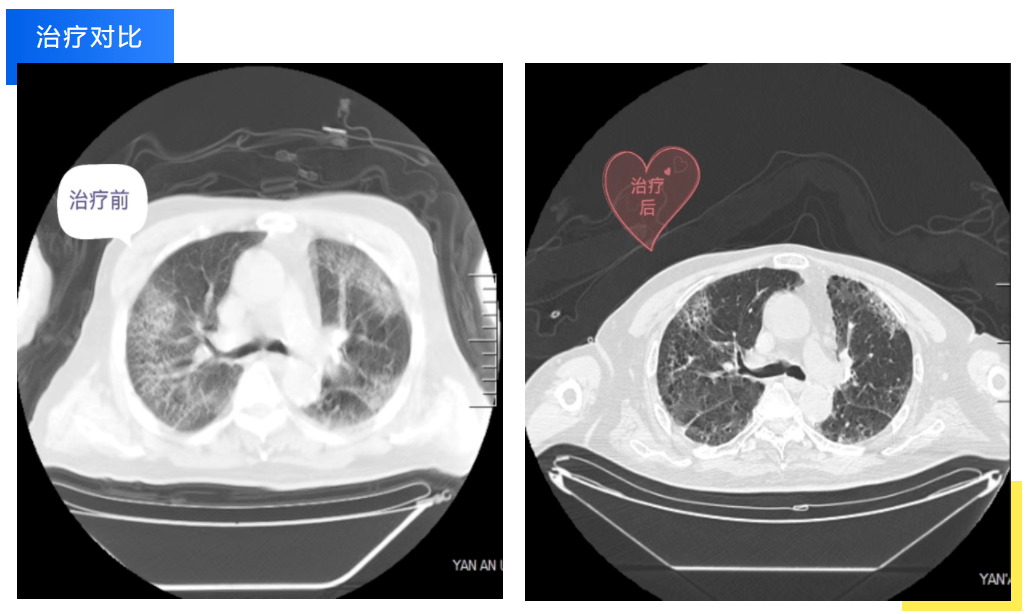

近期,患者张爷爷因重症肺炎入住我院重症医学科。入院时,老人的病情已经进展为严重呼吸衰竭合并双侧胸腔积液,住院期间老人因对病痛的恐惧和对医护工作的不理解而异常躁动不安,对诊疗及护理工作配合度极低,导致早期治疗效果并不理想。重症医学科宋海刚主任带领医护团队组织了科室疑难病例讨论、全院多学科会诊,张燕护士长、主管医生屈曼曼细致地观察病情,迅速梳理病情,调整诊疗方案,给予气管插管、机械通气、俯卧位通气、抑制炎症反应等综合治疗。

经过数日的治疗和精心护理,老人呼吸衰竭的指标较前有了明显的改善,氧合指数也从一开始的小于100mmHg逐渐提升到300mmHg以上,老人也感受到了医护人员的良苦用心,从开始的抗拒到逐渐主动配合诊疗工作,目前已顺利转入下级医院继续康复。